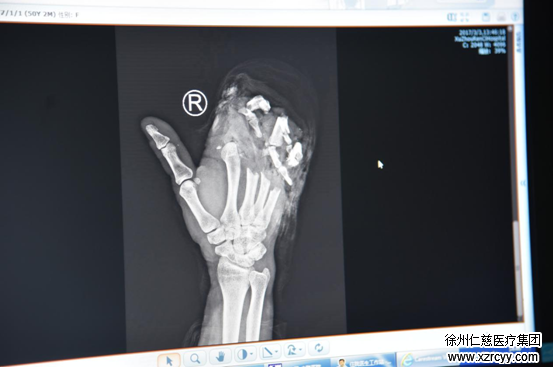

经诊断,褚女士掌骨骨折,2-4指毁损。

褚女士的手术医生,betway在线登陆手外一李刚介绍,褚女士的手掌考虑进行一期清创手术。他表示,因操作机器不慎受伤的病例,屡见不鲜。对于悲剧的发生,他们感到很痛心。同时希望通过媒体提醒市民:操作绞肉机、压面机过程中,切不可直接用手按压,以防酿成悲剧。